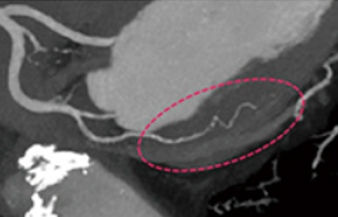

全脳Perfusionとは造影剤を急速静注しながら連続的にCT撮影を行い、CT断面上での吸収値の変化を解析することによって、脳の血流を定量的に評価する検査法です。短時間かつ簡便な手法で精度の高い脳血流情報を得ることができるので、治療方針の決定やその経過観察に有用な検査法です。

4DCTは従来の3次元画像に時間軸が加わり、血行動態の評価が可能となります。動脈や静脈の血流を連続画像として得ることができるので、動静脈奇形などの診断に有用です。

3D画像

撮影した画像から・・・

3D画像は撮影したCT画像を立体的に表示できるため、直感的に解剖学的情報や骨折部位などを把握することができ、診断や治療の助けになっています。出血や脳梗塞などによる緊急IVR検査を迅速に正確に行う為にもとても重要な画像です。